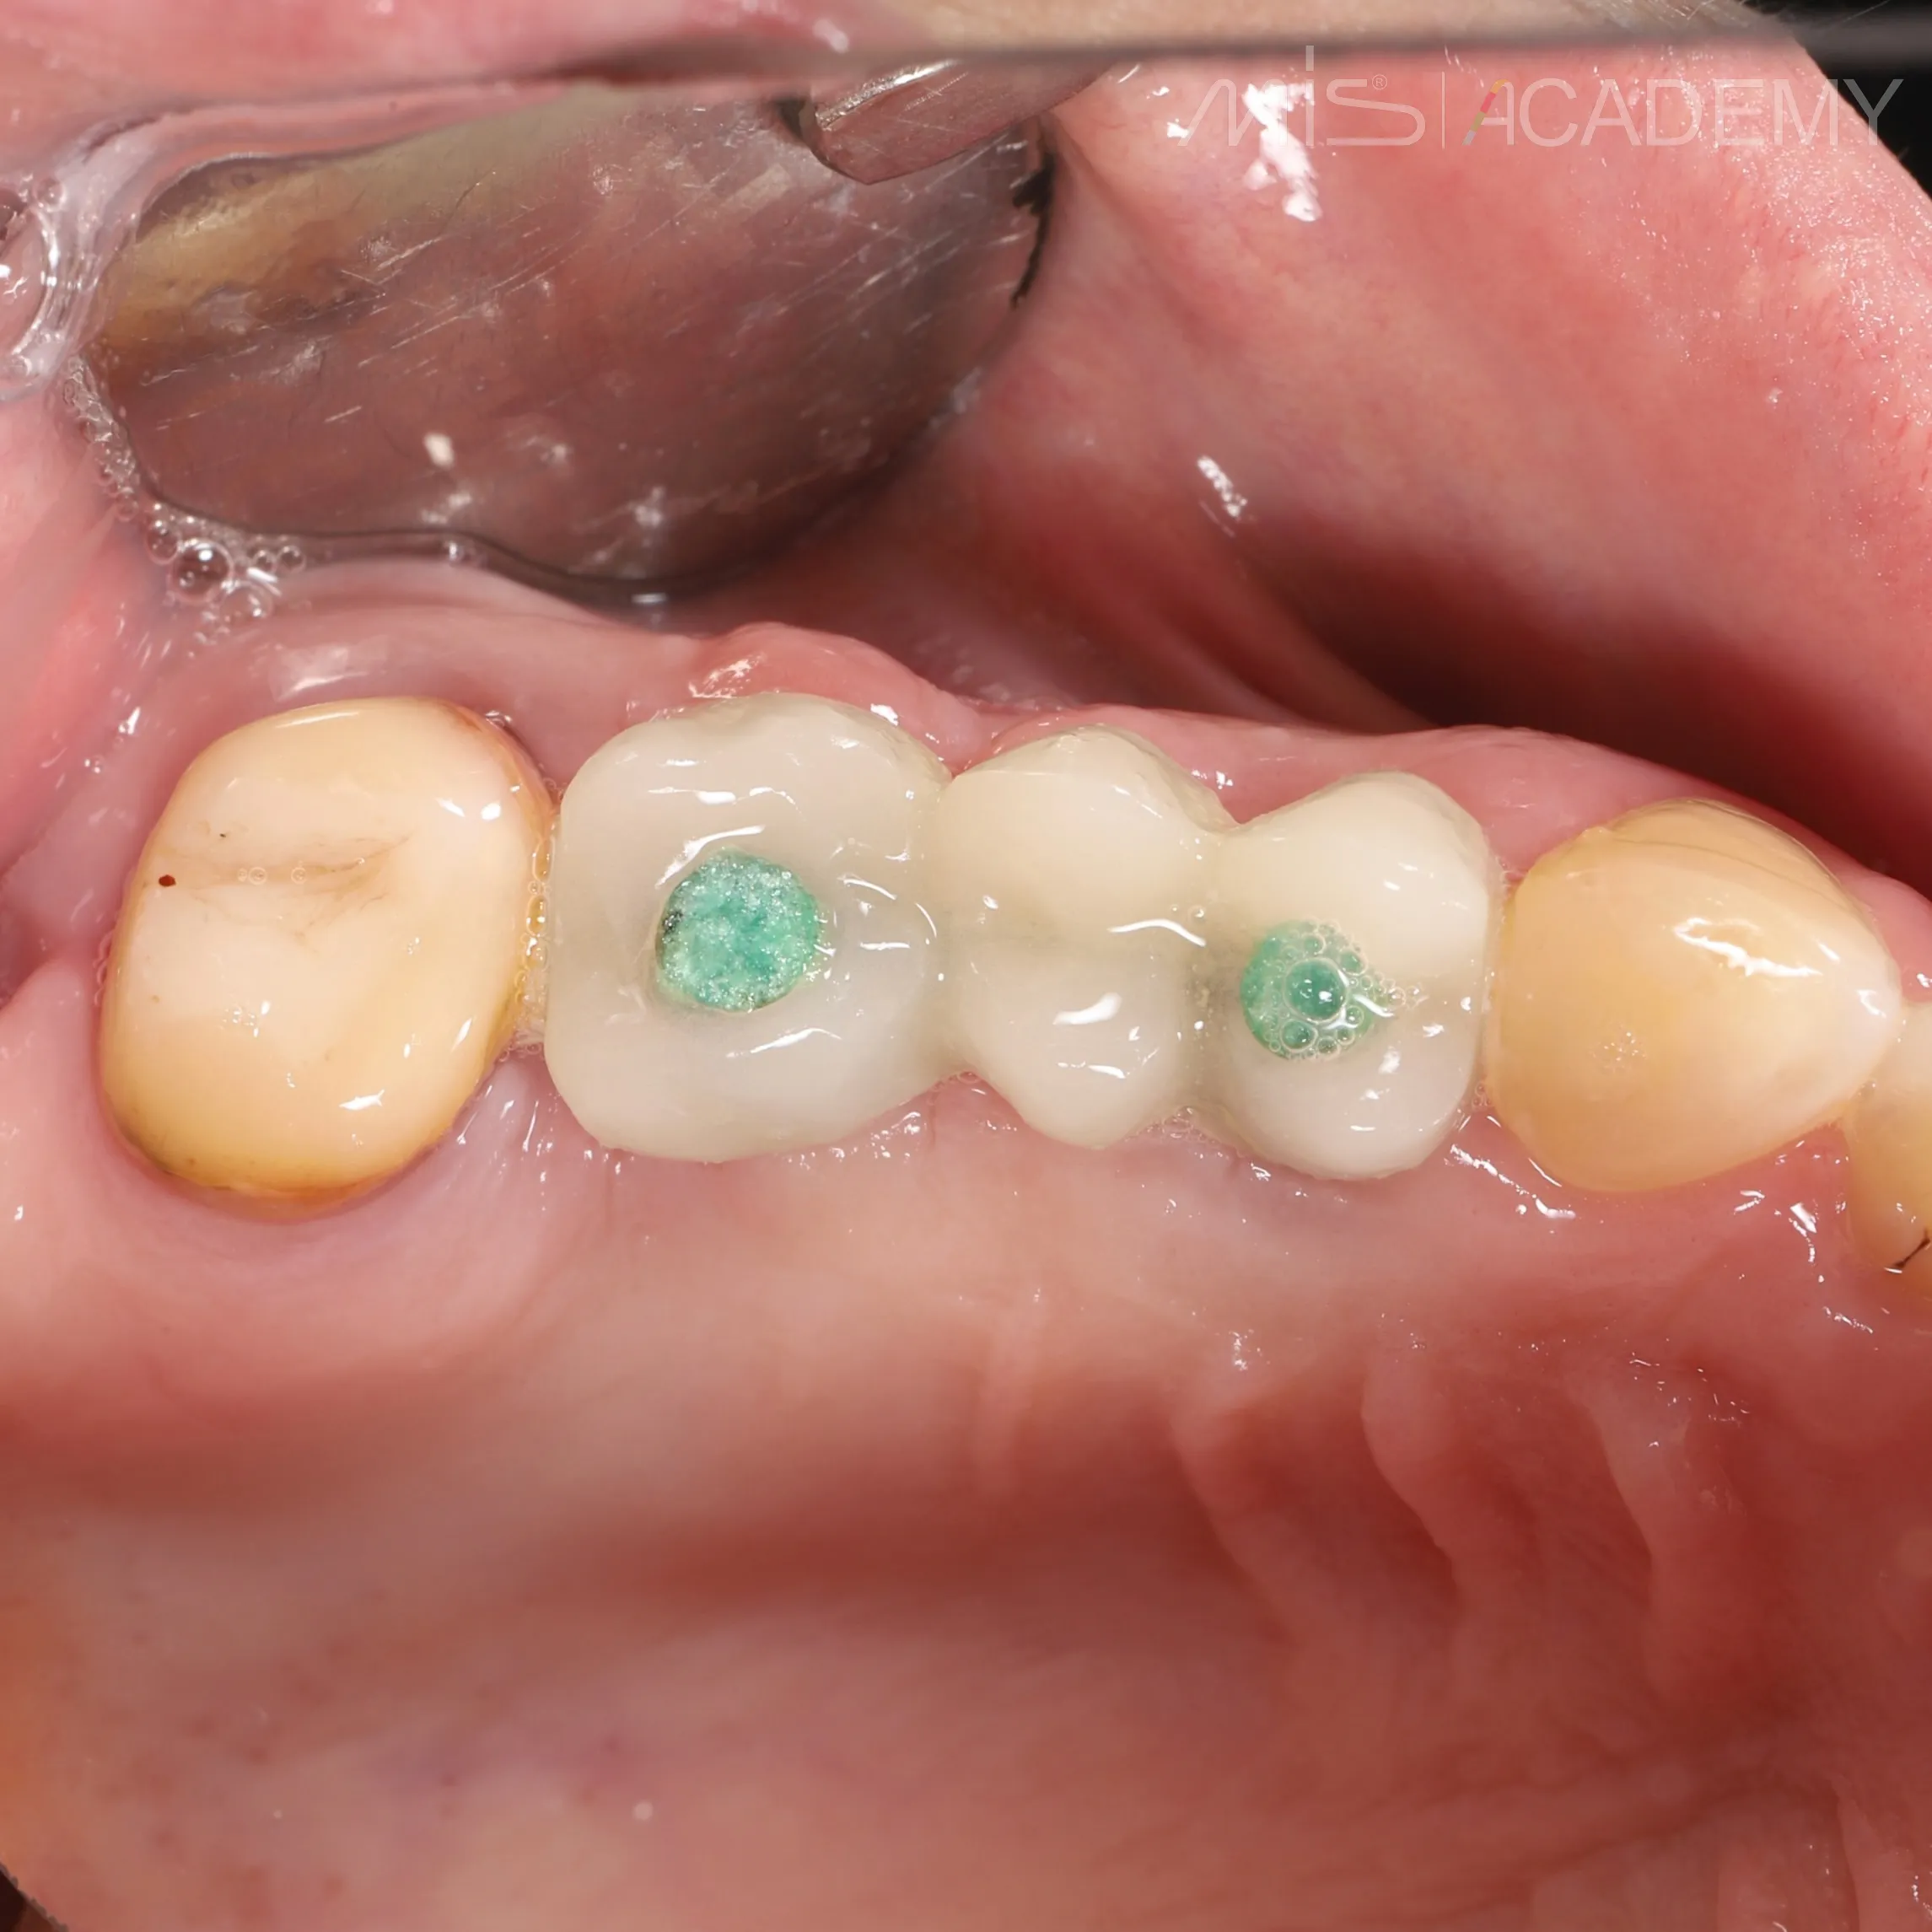

— Фиксация балки lego bridge + внутриротовая сварка.

— Временные коронки.

P/S Заживление через 3 месяца.